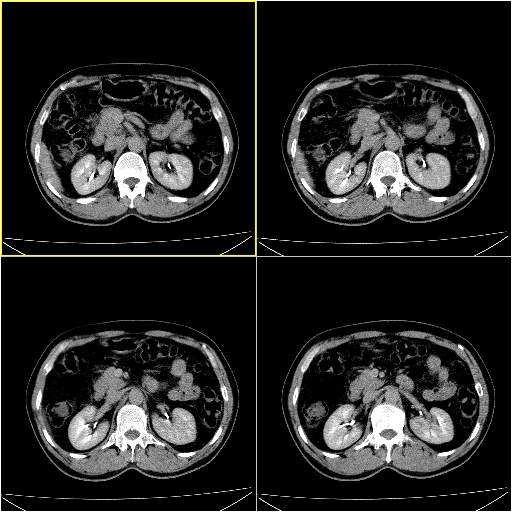

男性,54岁,皮肤黄染,搔痒一周余.b超示肝左叶回声异常.初步诊断1胆总管下段结石2胆囊结石伴慢性胆囊炎请各位战友帮忙看一下肝脏多发低密度如何解释恰当.增强效果不是很好.请大家见谅.

首先,胆总管下端结石梗阻伴肝内胆管扩张可确定。

其次,增强动脉期肝静脉显影,肝实质密度不均。——此为右心功能不全引起肝淤血的表现。

另外,肝八段低密度占位,呈多灶性,考虑肝脓肿或肝癌可能,(图像质量欠佳)建议进一步检查。

既然做了增强,为什么光提供延时期片子,肝动静脉期肝右叶前下段病灶增强如何?另外胆囊壁增厚,欠规整,内密度不均,与肝右叶病灶分界不清,增强表现怎样?肝内胆管轻度扩张,胆总管扩张,但未见明显结石影,也应提供增强早期图像才好鉴别扩张原因。片子较清,但不够完整,暂考虑1.胆囊癌肝局部浸润,或肝癌胆囊侵犯,2.胆总管下端或胰头钩突部占位。总之本人看不明白,请高手画图指示,先谢了!

由于胆囊窝内结构显示不清,肝脏病灶又邻近胆囊窝首先考虑胆囊癌肝受侵犯。而后因肝脏病灶强化有渐进改变,且相邻胆管扩张,故考虑肝胆管细胞癌待排。

左肝胆管细胞癌。

胆总管下端结石。